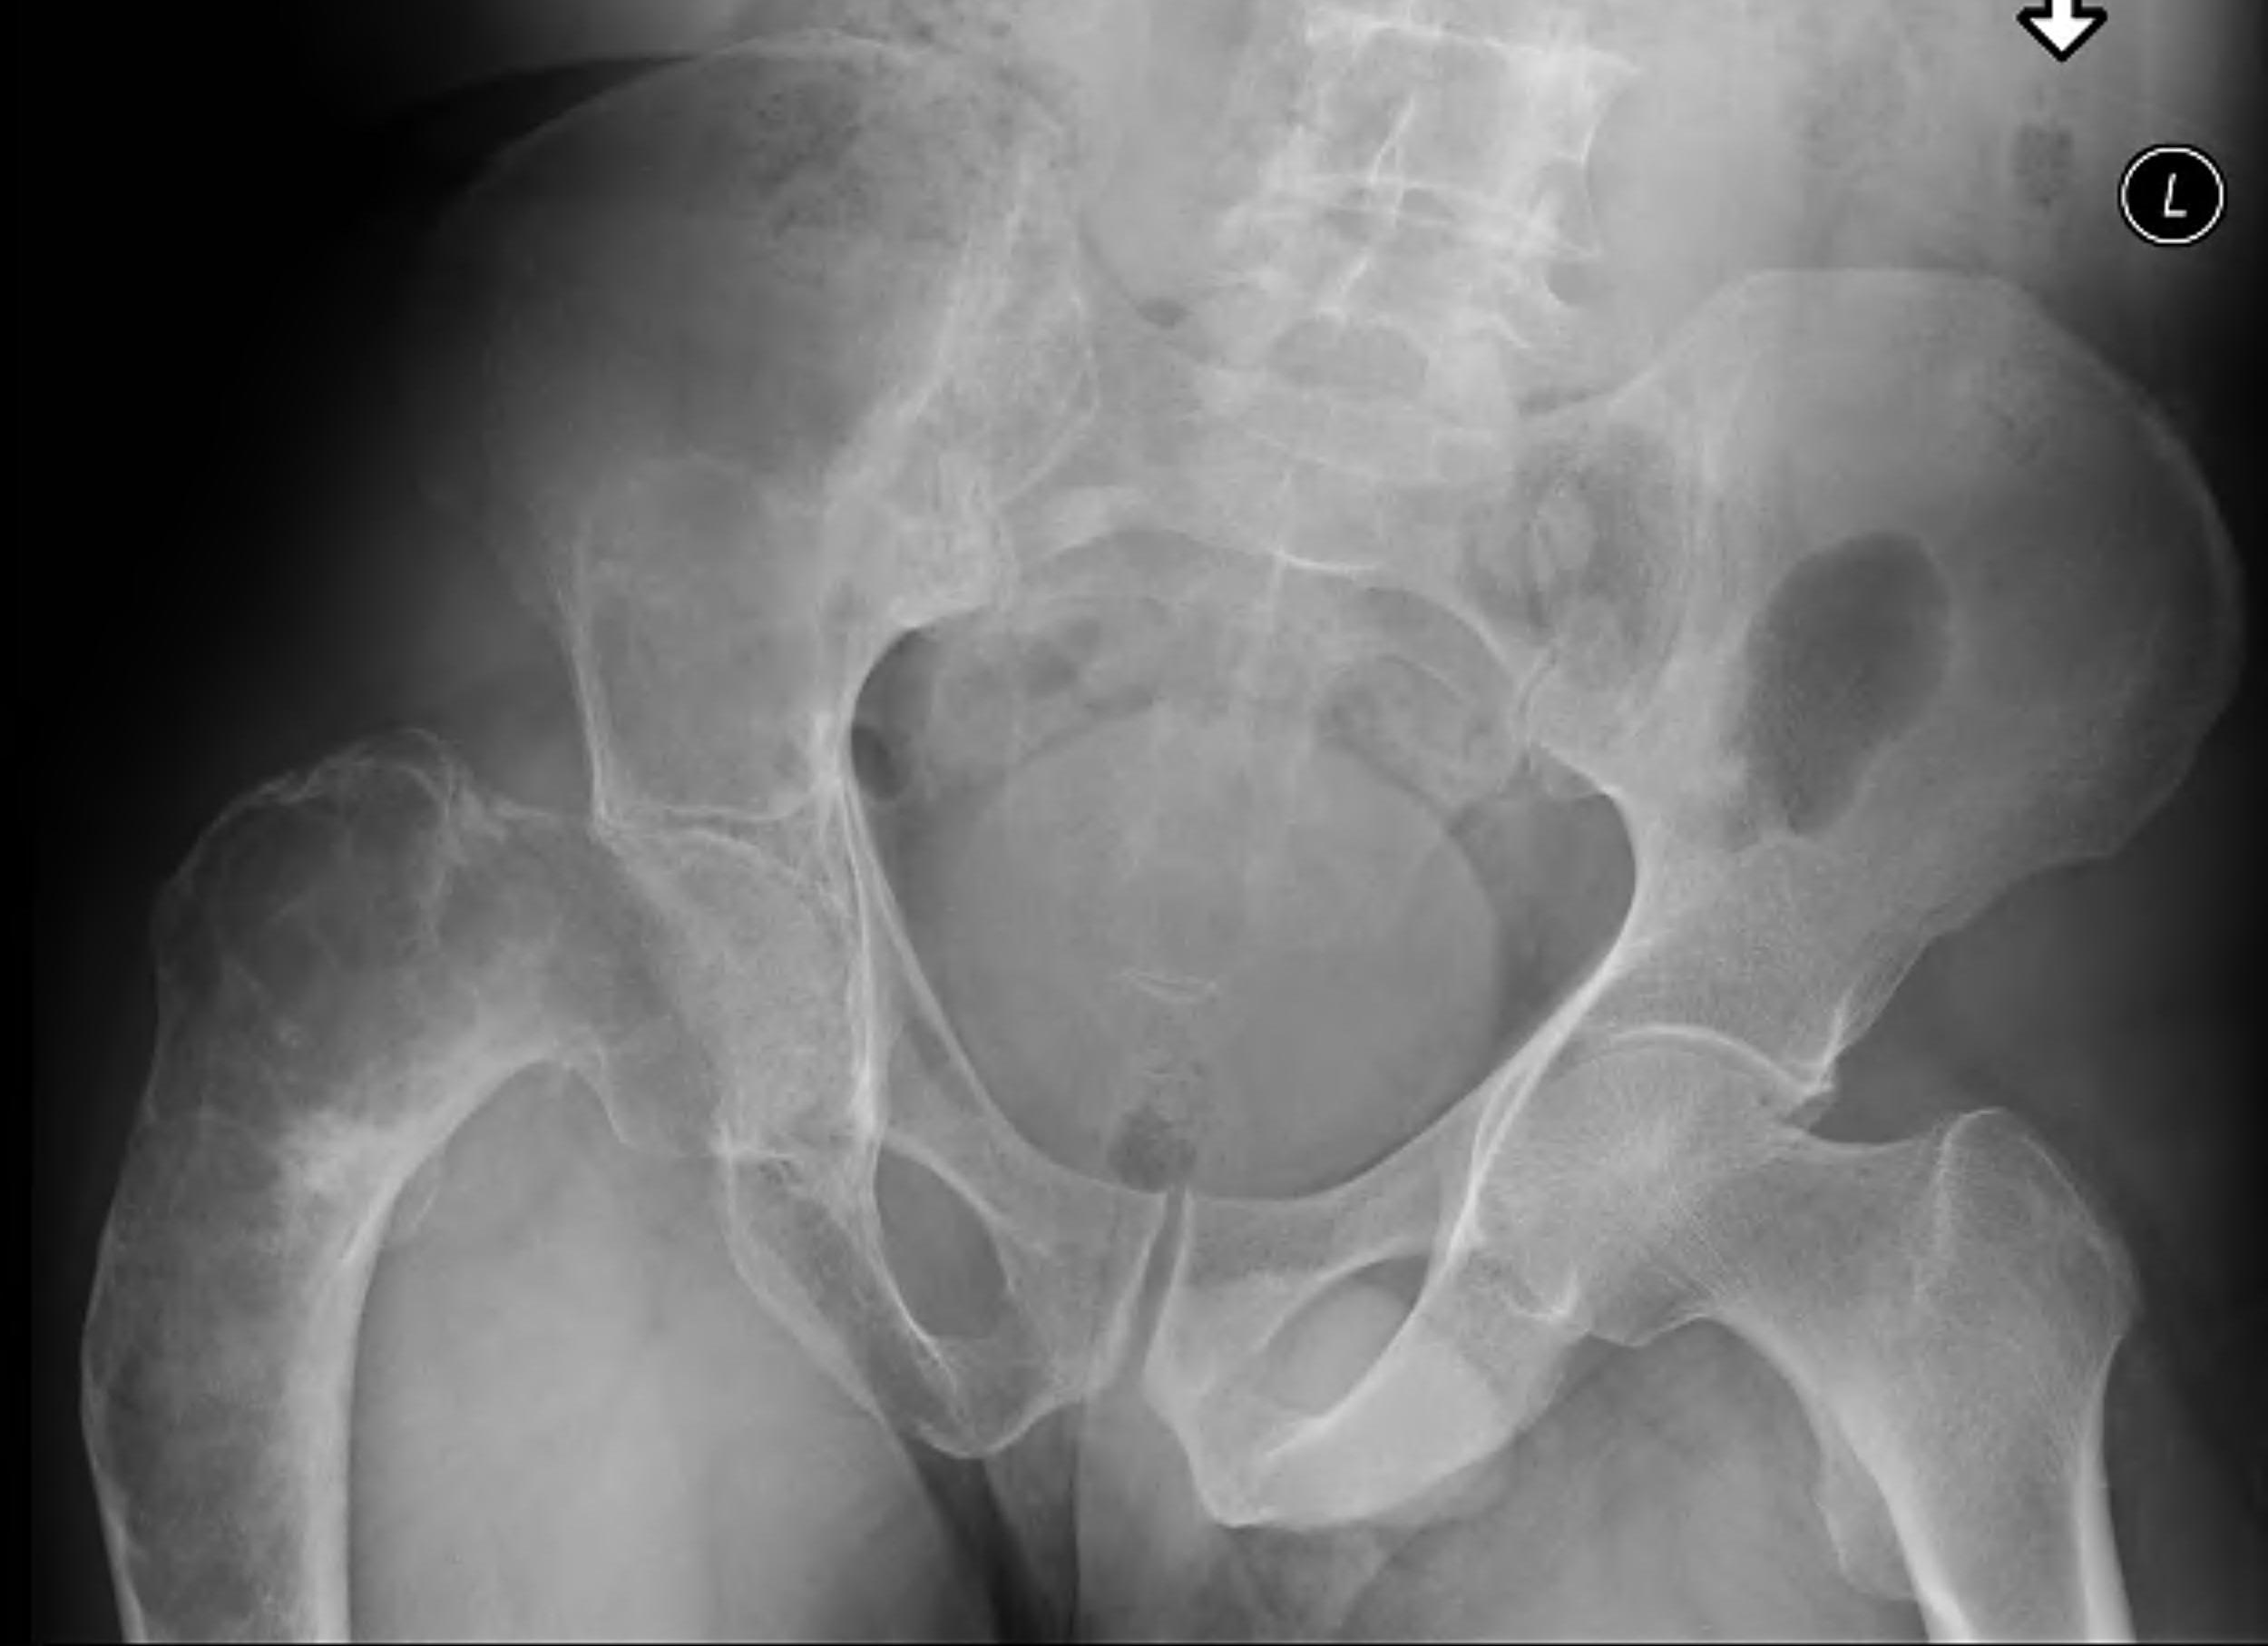

Intramedullary lucent diaphyseal lesion with 'ground glass appearance'

- thinned, slightly bulged cortex

- ± endosteal scalloping

- may have angular deformity / bowing

Coxa vara and Shepherd's Crook deformity of proximal femur

- Shepherd's Crook - anterior bowing of femur